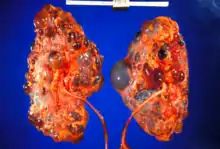

| |

| Polycystic kidneys | |

Adult polycystic kidney

Adult polycystic kidney Diagram of autosomal dominant polycystic disease with a normal kidney inset for comparison